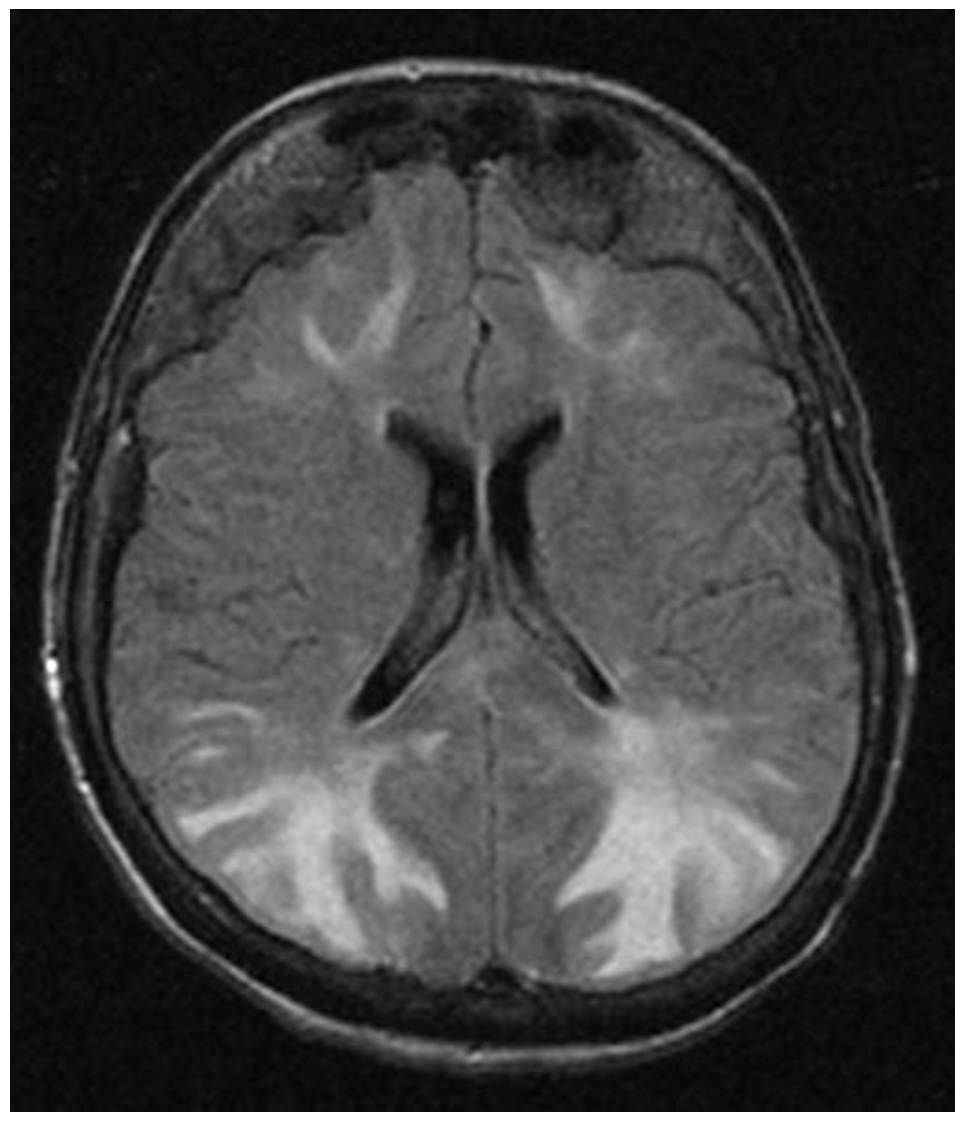

- hypertensive encephalopathy : 임상진단으로 심한 고혈압을 보이는 환자에서 의식변화, 두통, 구토, 경련, 시야 장애가 있는 경우 의심할 수 있으며, 다른 가능성 있는 진단들을 배제하여 진단하게 된다. 안저검사에서 papilledema(유두부종) 소견을 보이며, MRI 검사를 시행하였을 때 주로 대뇌 후두부(occipital lobe) 쪽으로 부종 소견이 보이며, 이를 posterior reversible encephalopathy syndrome(PRES)라고 한다.

| hypertensive encephalopathy | 의식 변화, 오심/구토, 두통 | 안저검사 이상 소견(papilledema/anterior hemorrhage/exudate), brain MRI |